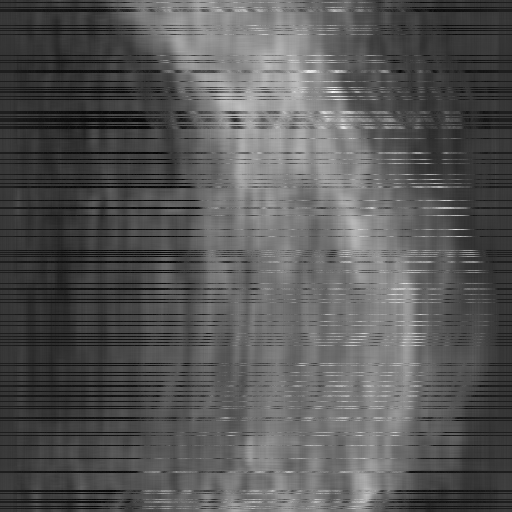

Figure 2: Qualitative inpainting results on TomoBank (lines 1 to 2) and LoDoPaB (lines 3 to 4) with random mask (ratio = 0.8) at 1024×\times1024 resolution. Odd columns and even columns show the sinograms and reconstructed images, respectively.

Inpainting Quality. Tab 2 summarizes accuracy results. At 2048×\times2048 resolution, HiSin achieves the best performance among all baselines while remaining memory-efficient, demonstrating its ability to extend high-quality inpainting to resolutions where other diffusion models fail. At 1024×\times1024, HiSin delivers accuracy comparable to its computation-intensive counterpart RePaint, showing that our optimizations do not compromise fidelity at moderate scales. Compared to DiffIR and HiDiffusion, HiSin consistently achieves higher SSIM and PSNR across mask ratios, with improvements up to +0.03 SSIM and +1.8 dB PSNR. Fig 2 visualizes sinogram inpainting and reconstructed images, where HiSin produces nearly indistinguishable results from RePaint. These findings confirm that HiSin fundamentally extends diffusion-based inpainting to 2048×\times2048 resolution in a more memory- and runtime-efficient manner.